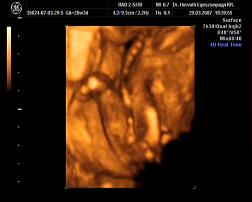

Mi meg megjöttünk az uh-ról, Ákosom nagyon szégyenlősvolt, már ami a kis arcát illeti, mert végig az arca előtt volt mindkétkeze, dörzsölte a szemét....néha profilból el lehetett kapni egy-egy pillanatot, szerintem gyönyörű...már olyan babás! Bezzeg a kukacát, azt mutogatta szorgosan! Meg megmutatta a kezeit, lábait, és hát néha a kis arcát is ki lehetett venni, de szemből teljesen most nem mutatta meg magát. De ami a legfontosabb, minden a legnagyobb rendben Vele, a gerince gyönyörű, gyomortelítődés szépen látható, vesék is szépek, koponya rendben....szóval minden okés, és ez a lényeg. Már 31O gramm a kis Drágám! Nagyon jó volt az egészvizsgálat, csak azt sajnálom, hogy nem sikerült képet készíteni Róla, pedig a doki mindent megtett...deDVD-t kaptunk, majd abból megpróbálok valamit kiügyeskedtetni Apával.

tegnap varézsoltam ki Nektek a DVD-ről olyan képeket, ahol nagyjából látszik Ákosom, erre elment a net... :evil: Űgyhogymost megpróbálom felrakni, aztán írok. :D

Apa "büszkesége" :D Kép

Kép